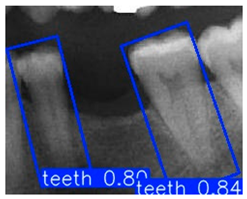

Although YOLOv10n-OBB demonstrated a slight advantage in overall classification accuracy, YOLOv8n-OBB achieved a relatively higher mAP50–95 of 78.75%. Furthermore, as illustrated in Figure 12, YOLOv8n-OBB generated predictions with higher confidence scores, and its detection boxes more comprehensively encompassed critical surrounding structures of the teeth, including both the crown and root regions. In contrast, YOLOv10n-OBB, despite exhibiting better classification accuracy, often produced detection boxes with insufficient coverage or positional deviations, which could compromise the accuracy and stability of subsequent localization and contour segmentation tasks. Considering both model performance and practical image application, the stable and reliable predictions provided by YOLOv8n-OBB better meet the requirements of fine-grained dental feature recognition. Moreover, its robustness is advantageous for downstream applications such as auxiliary line generation and implant pathway orientation.

Figure 12.

YOLO-OBB segmentation comparison.